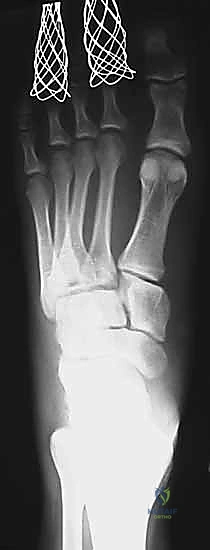

إصابة ليزفرانك: دليل شامل للتشخيص والعلاج الجراحي الدقيق في صنعاء مع الأستاذ الدكتور محمد هطيف

تعرف على إصابة ليزفرانك، أعراضها، تشخيصها، وخيارات العلاج الجراحي الدقيق في صنعاء. الأستاذ الدكتور محمد هطيف يقدم خبرته لضمان أفضل النتائج.